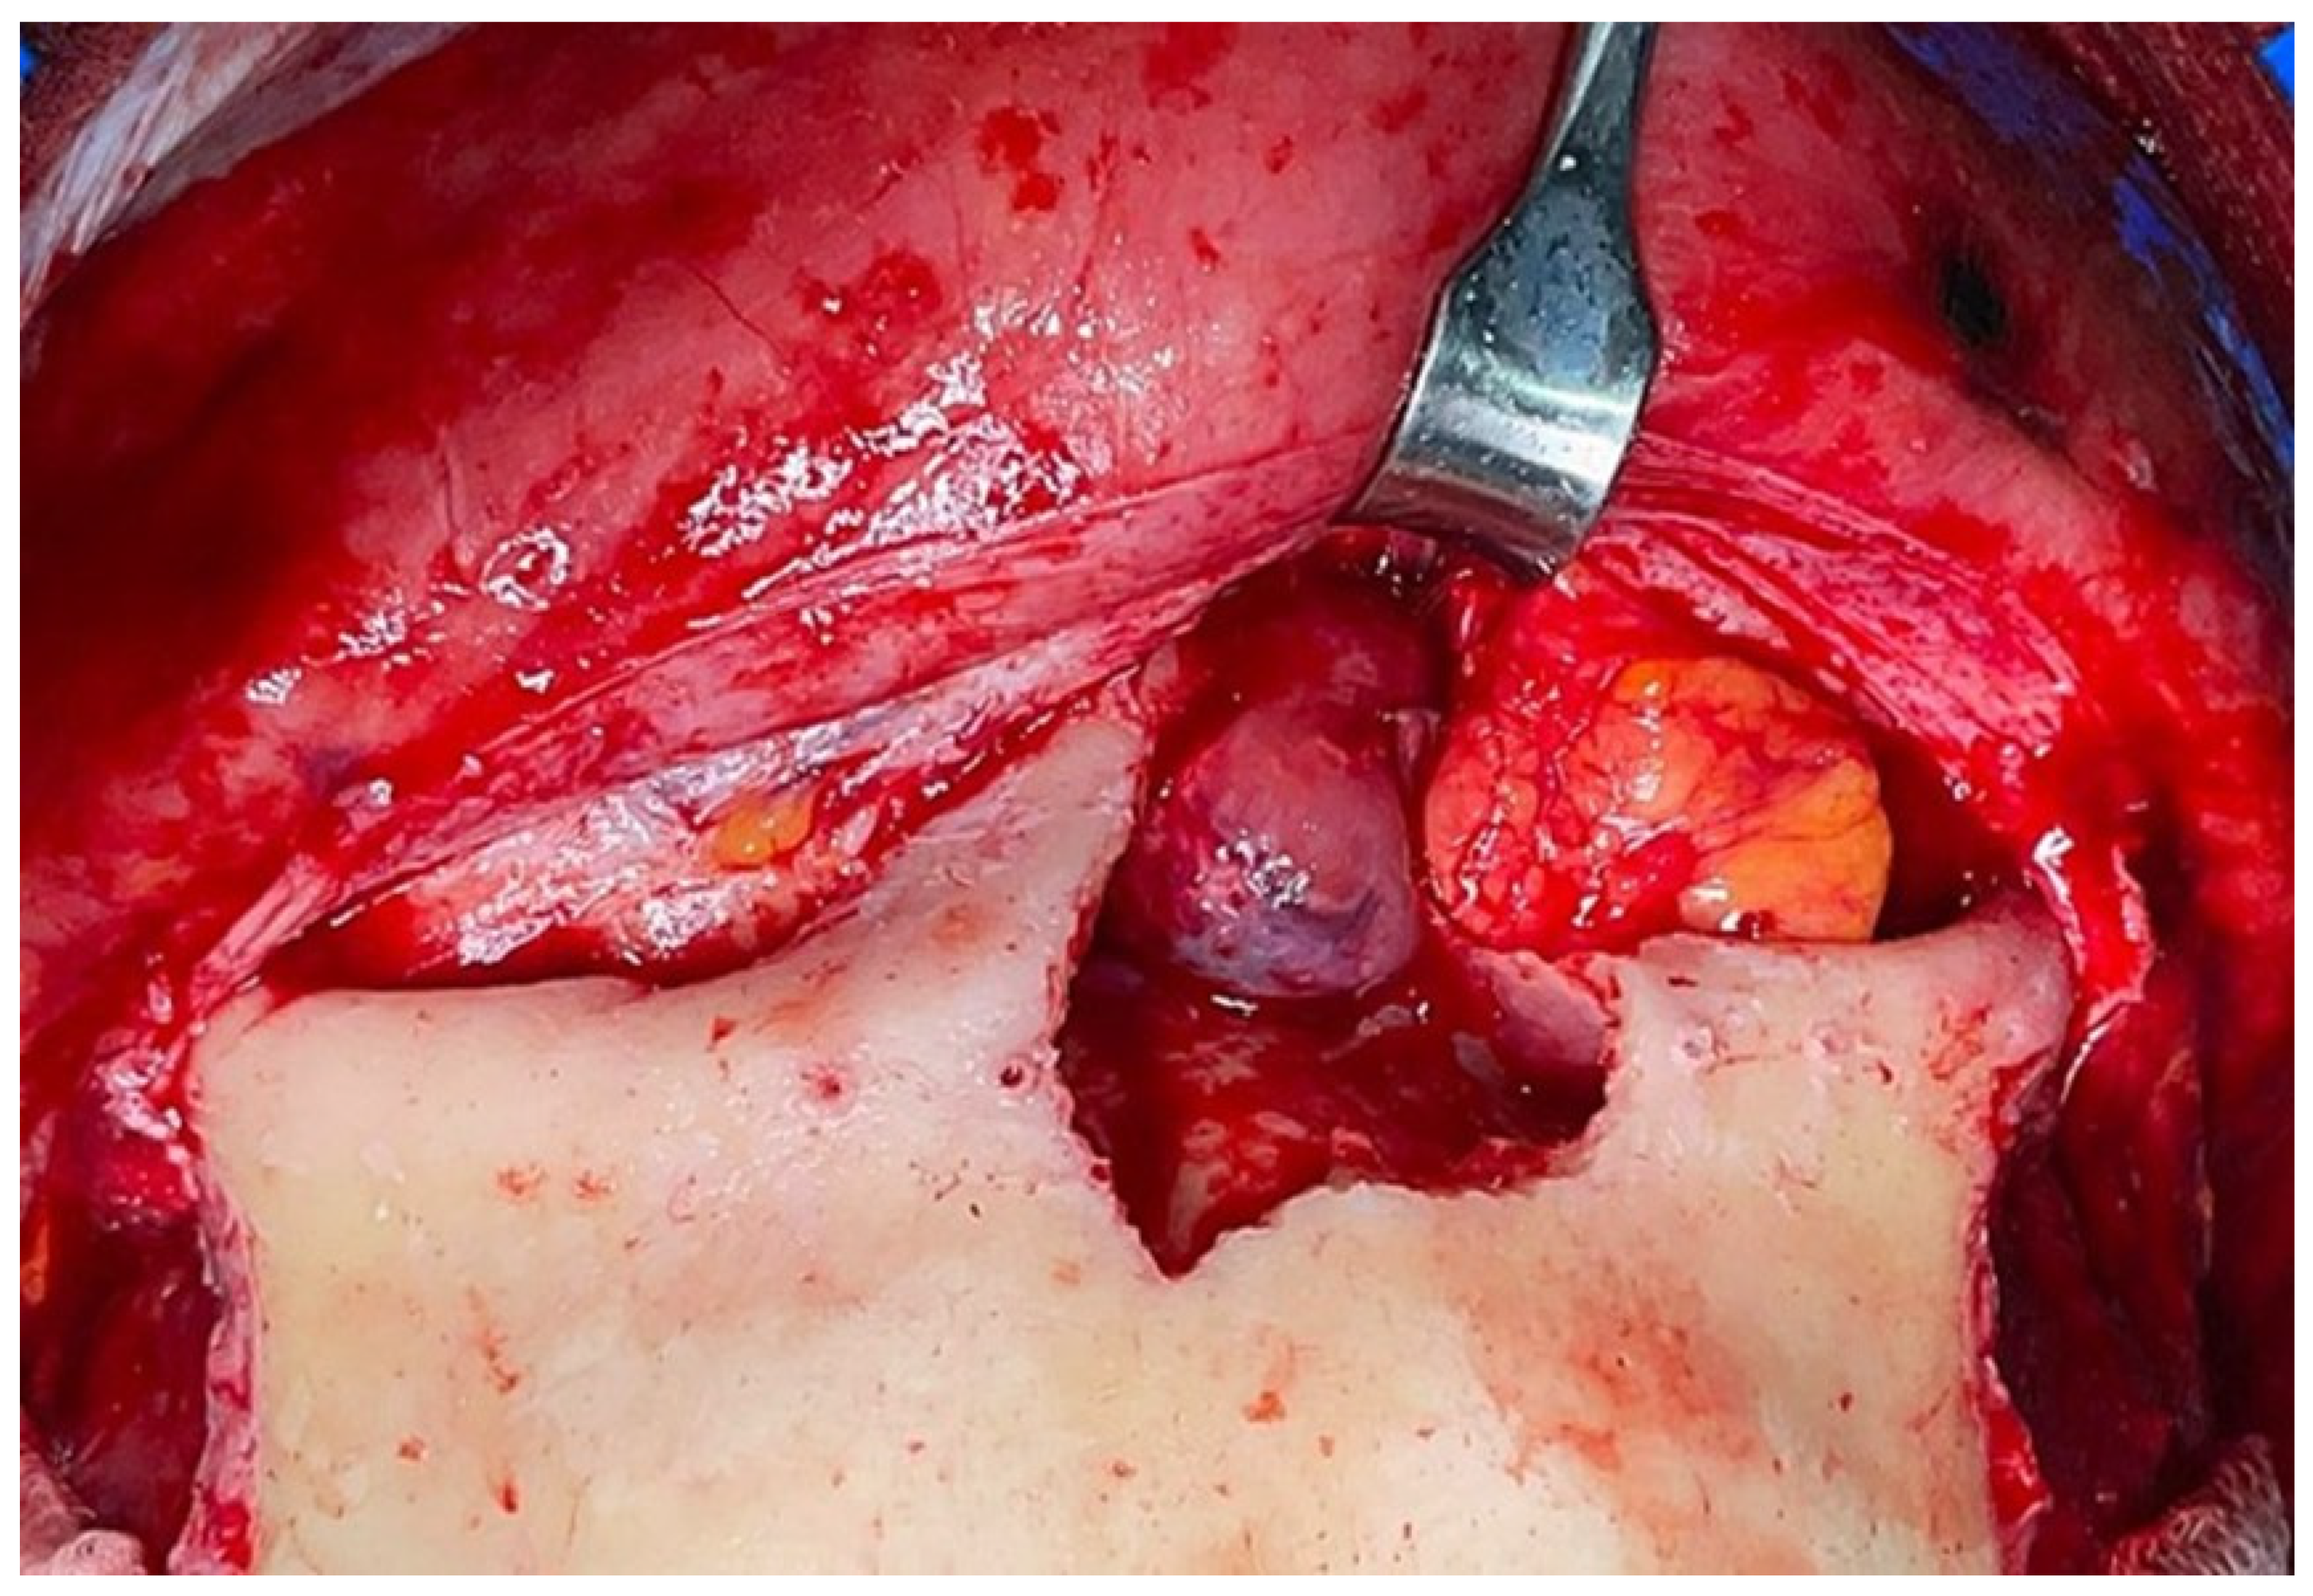

Figure 3.

Intraoperative view of the tumor through a trans-sinusal frontal approach.